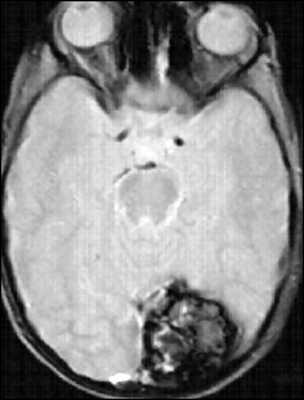

На МРТ паренхиматозные кавернозные ангиомы представлены характерным образованием по типу «попкорна», четко очерченным, с ровной границей. Внутренняя часть представлена множественными очагами сигнала различной интенсивности, которые соответствуют кровоизлияниям на разных стадиях разрешения.

![кавернозная ангиома мрт]()

МРТ-признаки кавернозной ангиомы. Крупные кавернозные ангиомы правой лобной доли и левой затылочной доли на Т1-взвешенном аксиальном срезе. У этих двух гетерогенных объемных образований отмечается сетчатая структура центральной части с чередованием участков высокой и низкой интенсивности сигнала, окруженная гипоинтенсивным ободком из гемосидерина.

Свежая гематома, содержащая дезоксигемоглобин, изоинтенсивна на Т1-взвешенных изображениях и значимо гипоинтенсивна на Т2-взвешенных изображениях. Подострая гематома, содержащая внеклеточный метгемоглобин, гиперинтенсивна как на Т1-, так и на Т2-взвешенных изображениях вследствие парамагнетического эффекта, оказываемого метгемоглобином.

Промежуточные фиброзные элементы характеризуются слабо гипоинтенсивным сигналом на Т1- и Т2-взвешенных изображениях, поскольку содержат кальцификаты и гемосидерин. Гетерогенная внутренняя часть образования окружена гемосидериновым ободком, обладающим низкой интенсивностью на Т1-взвешенных изображениях. Гипоинтенсивность этого ободка становится более выраженной, напоминающей ореол, на Т2-взвешенных изображениях и изображениях в режиме градиентного эха благодаря более высокой чувствительности этих последовательностей к изменениям магнитного поля.

![кавернома мрт]()

Аксиальные МРТ-изображения в режиме градиентного эхо позволяют достичь лучшей визуализации крупных кавернозных ангиом в правой лобной и левой затылочной долях. Гемосидериновый ободок представлен в виде ореола вследствие повышенной магнитной восприимчивости гемосидерина.